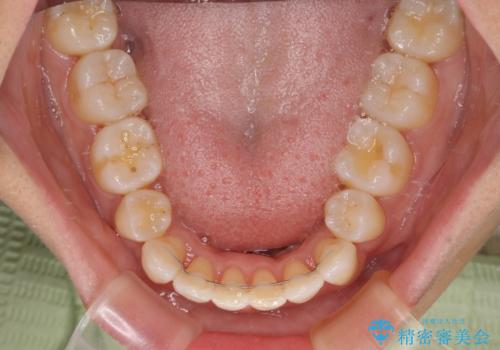

抜歯スペースに前歯を移動させることで歯の突出感が改善され、非常に唇が閉じやすい仕上がりとなりました。